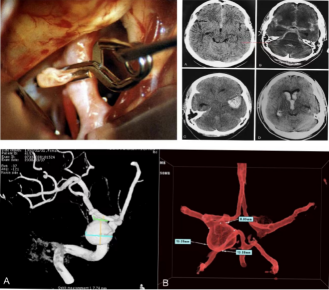

腦血管病及功能神外亞專業(yè)能夠開展腦動脈瘤、腦血管畸形的顯微手術(shù)治療,能夠開展腦動脈瘤及缺血性腦血管病的血管內(nèi)接入治療,能夠進行常規(guī)開顱及神經(jīng)內(nèi)鏡下腦內(nèi)血腫清除術(shù),可以利用立體定向技術(shù)完成顱內(nèi)各個部位的血腫穿刺治療,能夠熟練開展三叉神經(jīng)痛/面肌痙攣微血管減壓等多種功能神經(jīng)外科手術(shù)。